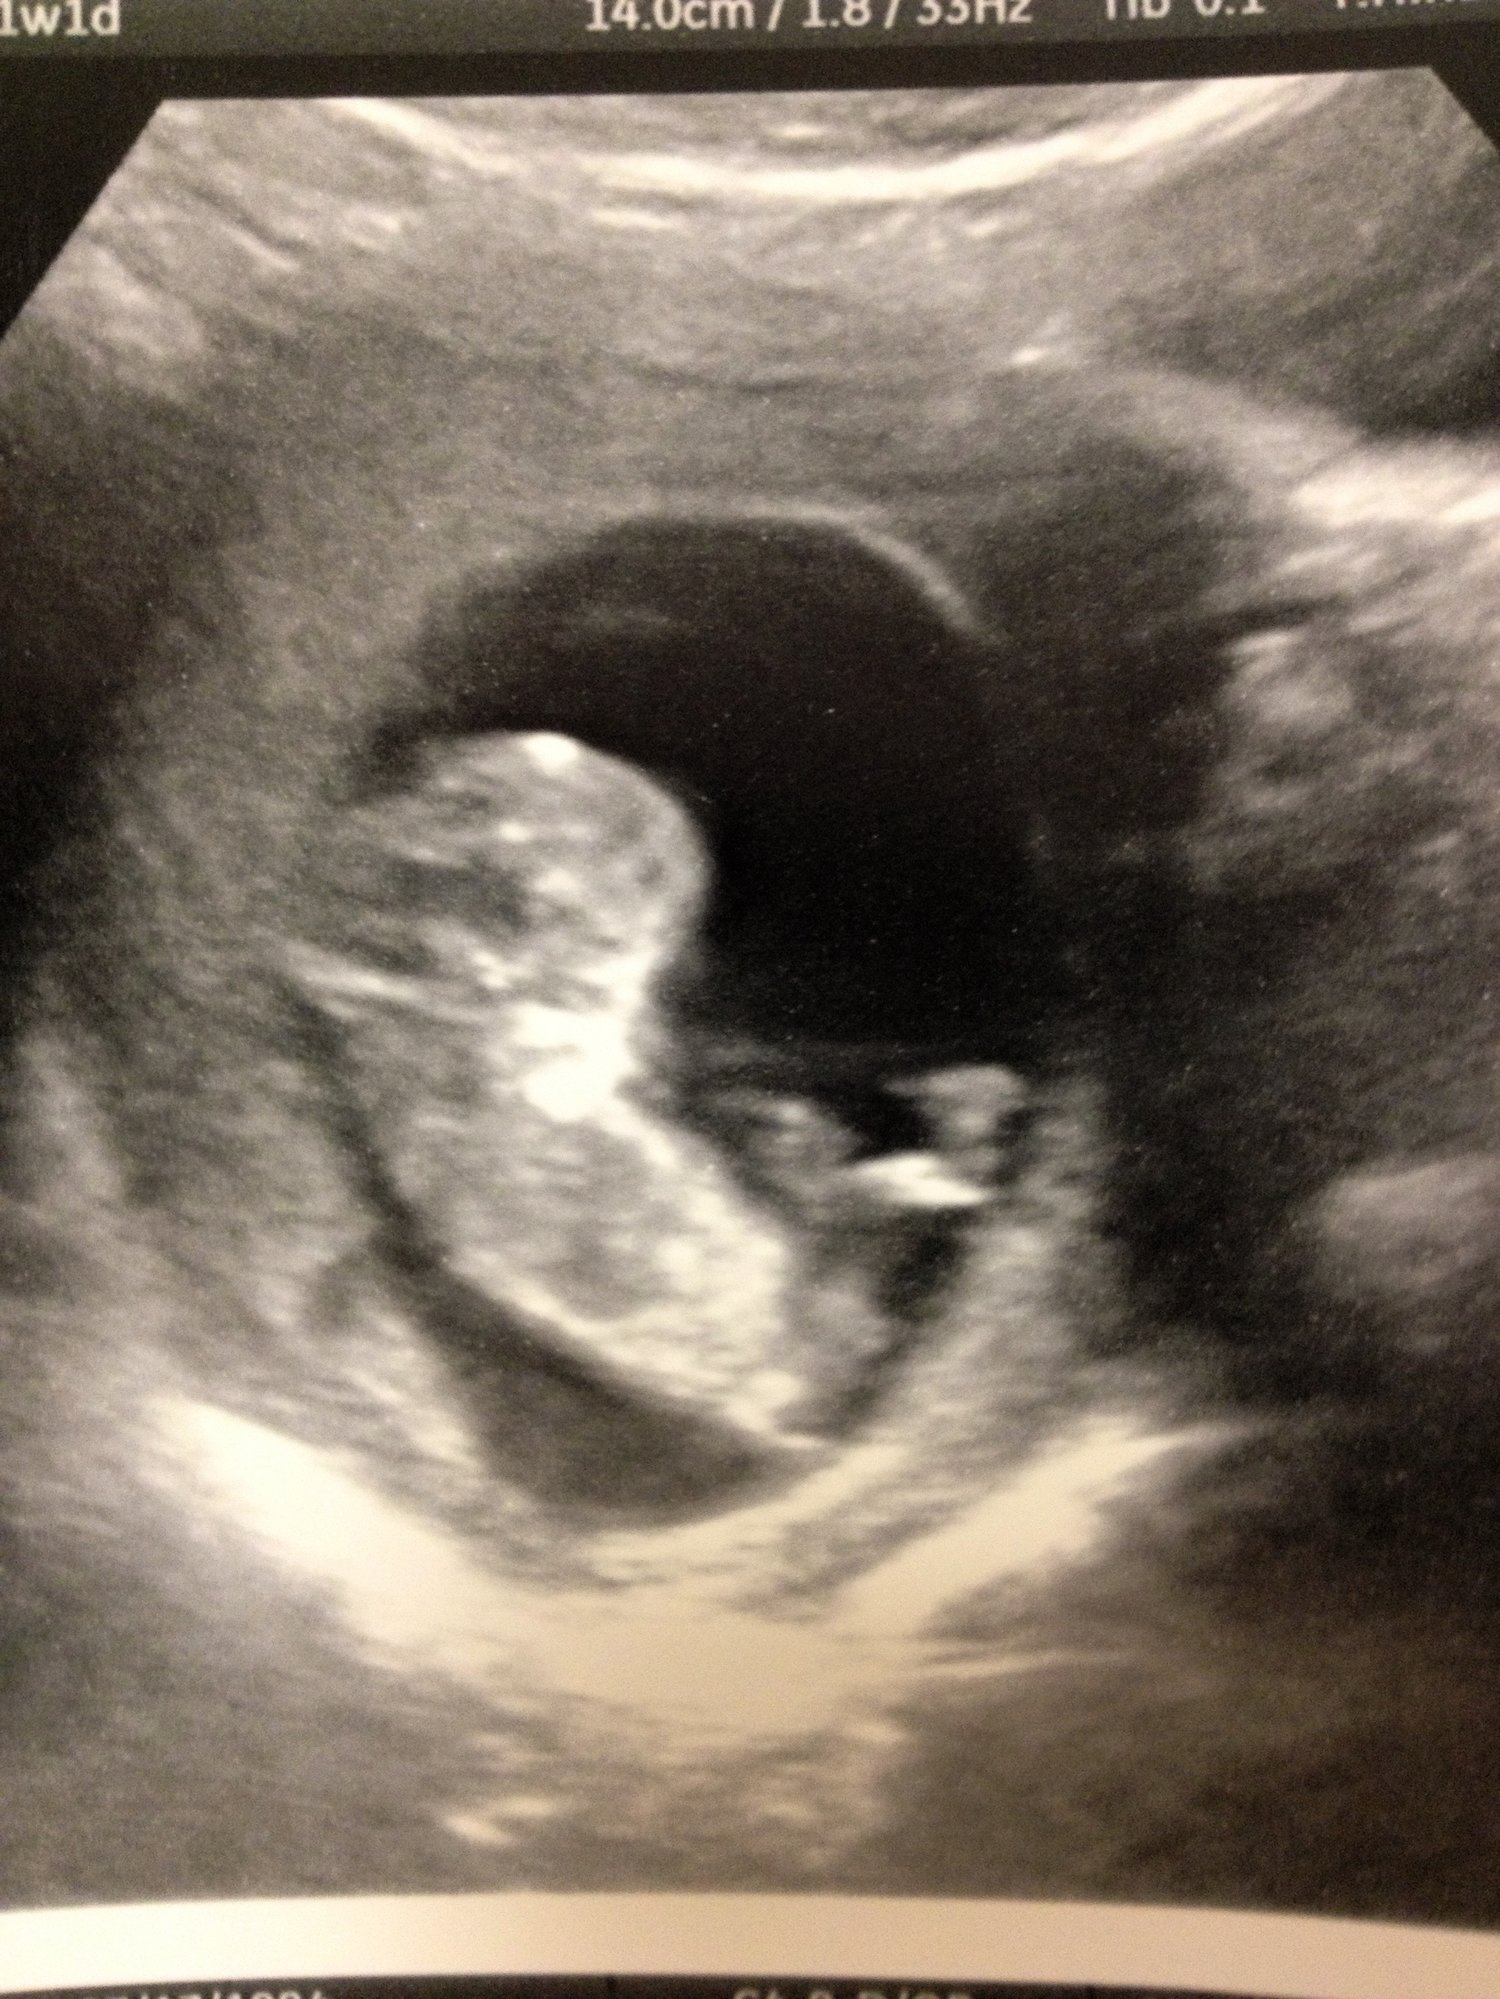

I'm sorry for being such a special snowflake, and I'm sorry the image is so huge (don't know how to resize), but I'm just so full of SQUEE! We had our second u/s this morning. I can't get over that little foot!